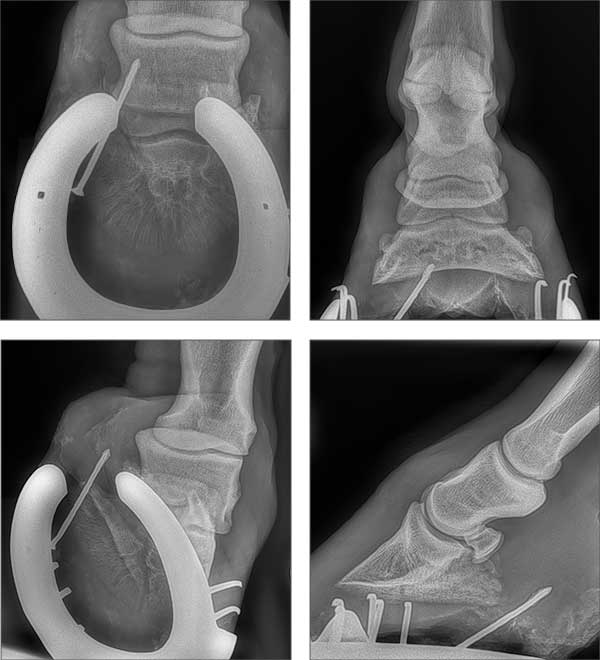

Unsere Praxis besitzt drei Systeme zur digitalen direkten Röntgenentwicklung. Ein umständliches Entwickeln der Bilder in der Praxis entfällt, innerhalb von Sekunden ist das Röntgenbild sicht- und auswertbar. Die Röntgenbilder können wir Ihnen per Email zukommen lassen.

Im Rahmen einer orthopädischen Untersuchung können wir zum Beispiel Sehnen, Sehnenscheiden oder Gelenke schallen und hierbei den Zustand der einzelne Strukturen beurteilen.